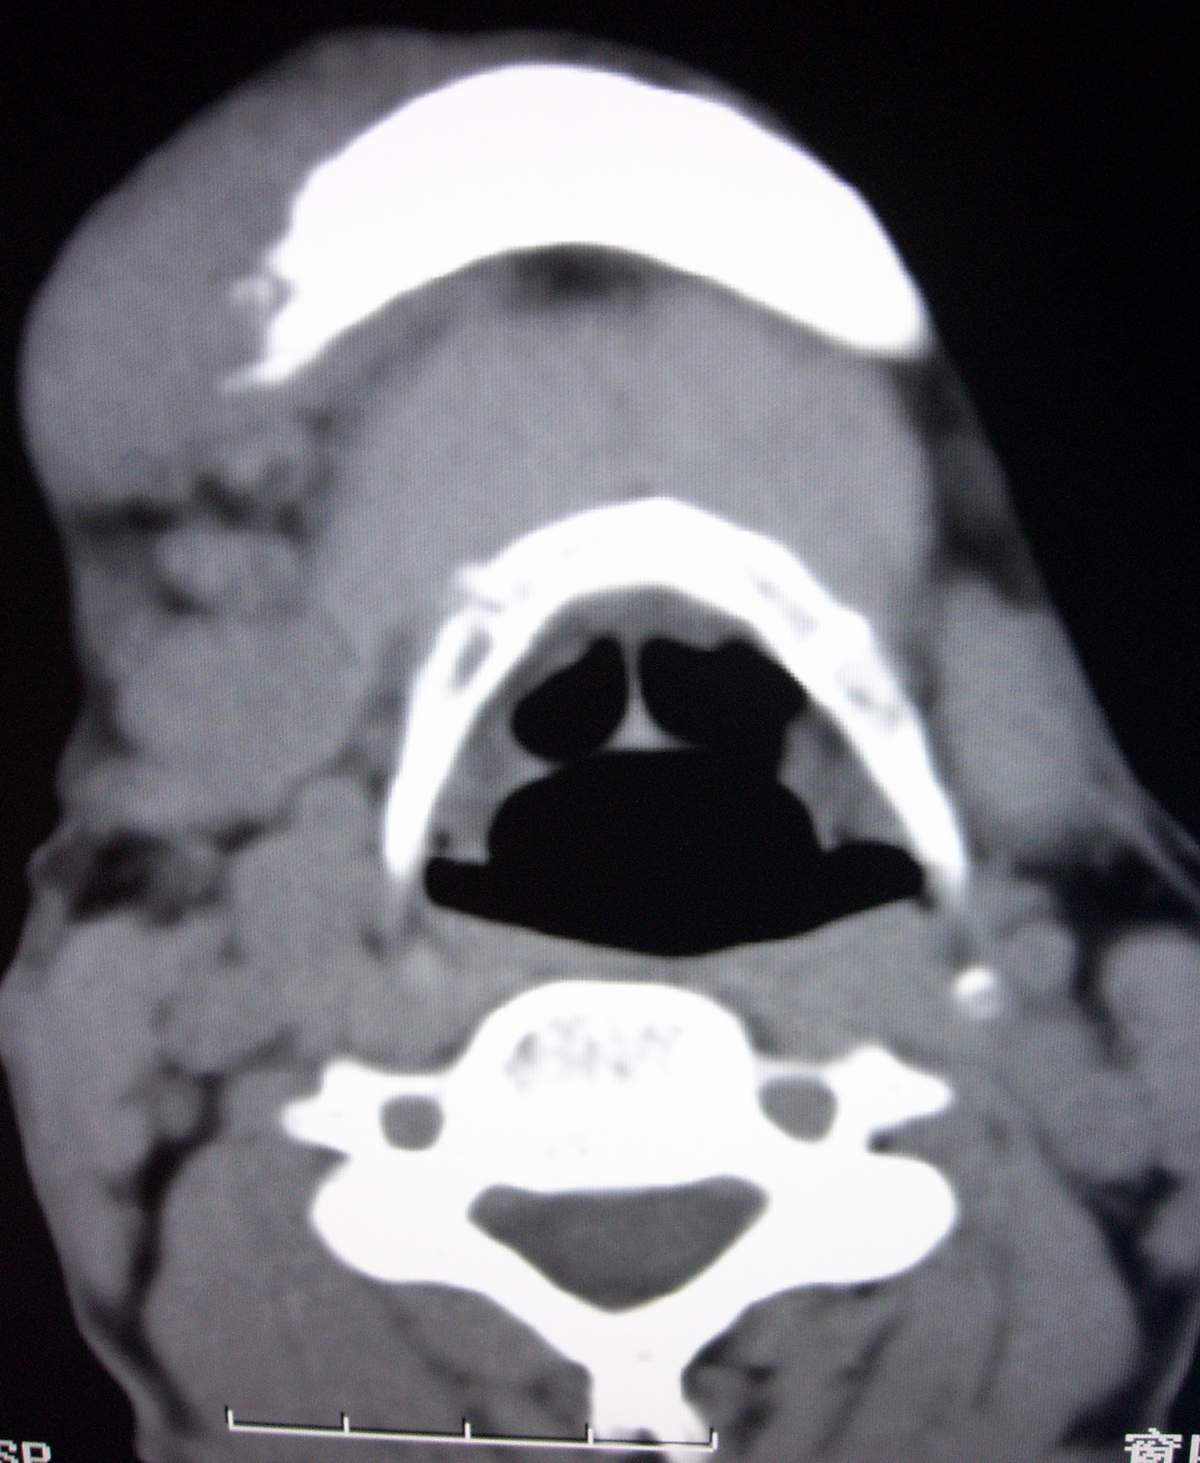

男,54岁,右下颌肿痛1月余。

右侧下颌骨水平部及升支呈溶骨性破坏,无明显膨胀,周围见软组织肿块。

考虑:右侧下颌骨恶性肿瘤或转移瘤。

右下颌骨溶骨性破坏,代之以团块状软组织影,内有斑片状瘤骨,边缘骨质有少量骨膜反应,考虑:右下颌骨骨肉瘤。期待病理。